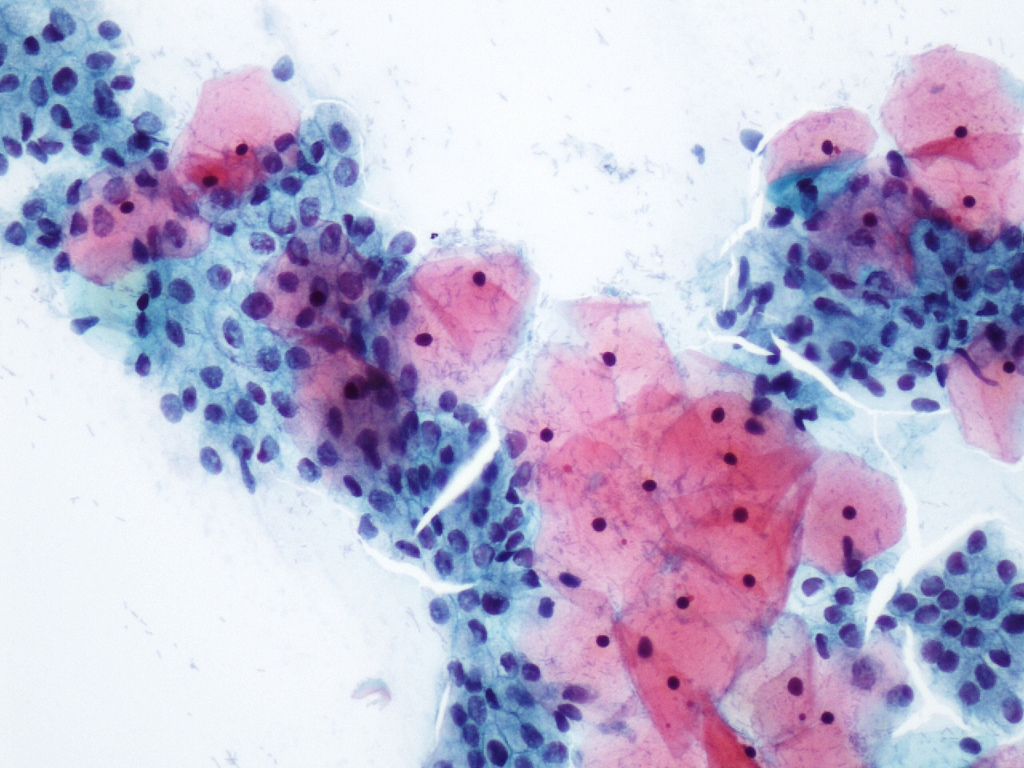

El trauma medular altera numerosos procesos celulares y moleculares con resultados letales para el tejido nervioso. Uno de estos procesos es la autofagia, un proceso de limpieza celular destinado a eliminar proteínas defectuosas y otra basura celular. Una alteración en este proceso provoca la acumulación de compuestos que interfieren con el normal funcionamiento de las células, llegando en último extremo a causar su muerte.

El trabajo, publicado en la prestigiosa revista ‘Frontiers in Cellular Neuroscience’, ha permitido caracterizar cómo cambia la autofagia a lo largo del tiempo tras la lesión medular, comparando los cambios en distintas regiones y en diferentes células nerviosas de la médula espinal dañada.

Los resultados del estudio ponen de manifiesto que las respuestas autofágicas son más complejas y dispares de lo que se pensaba hasta la fecha, capaces de proteger a algunas células y de inducir la muerte de otras.